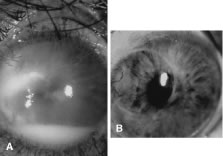

Candida infection typically produces epithelial ulceration, focal necrotizing stromal inflammation, moderate cellular infiltrate and edema in the adjacent stroma, and mild or moderate iritis in the early stages, indistinguishable from bacterial keratitis (Figs. 15, 16, and 17). Fungal elements cannot be detected by biomicroscopy. If untreated, the keratitis evolves to produce dense suppuration and necrosis of the deep stroma. Although multifocal suppuration may develop in polymicrobial keratitis, there is no distinctive sign of mixed Candida and bacterial infection (Fig. 18).